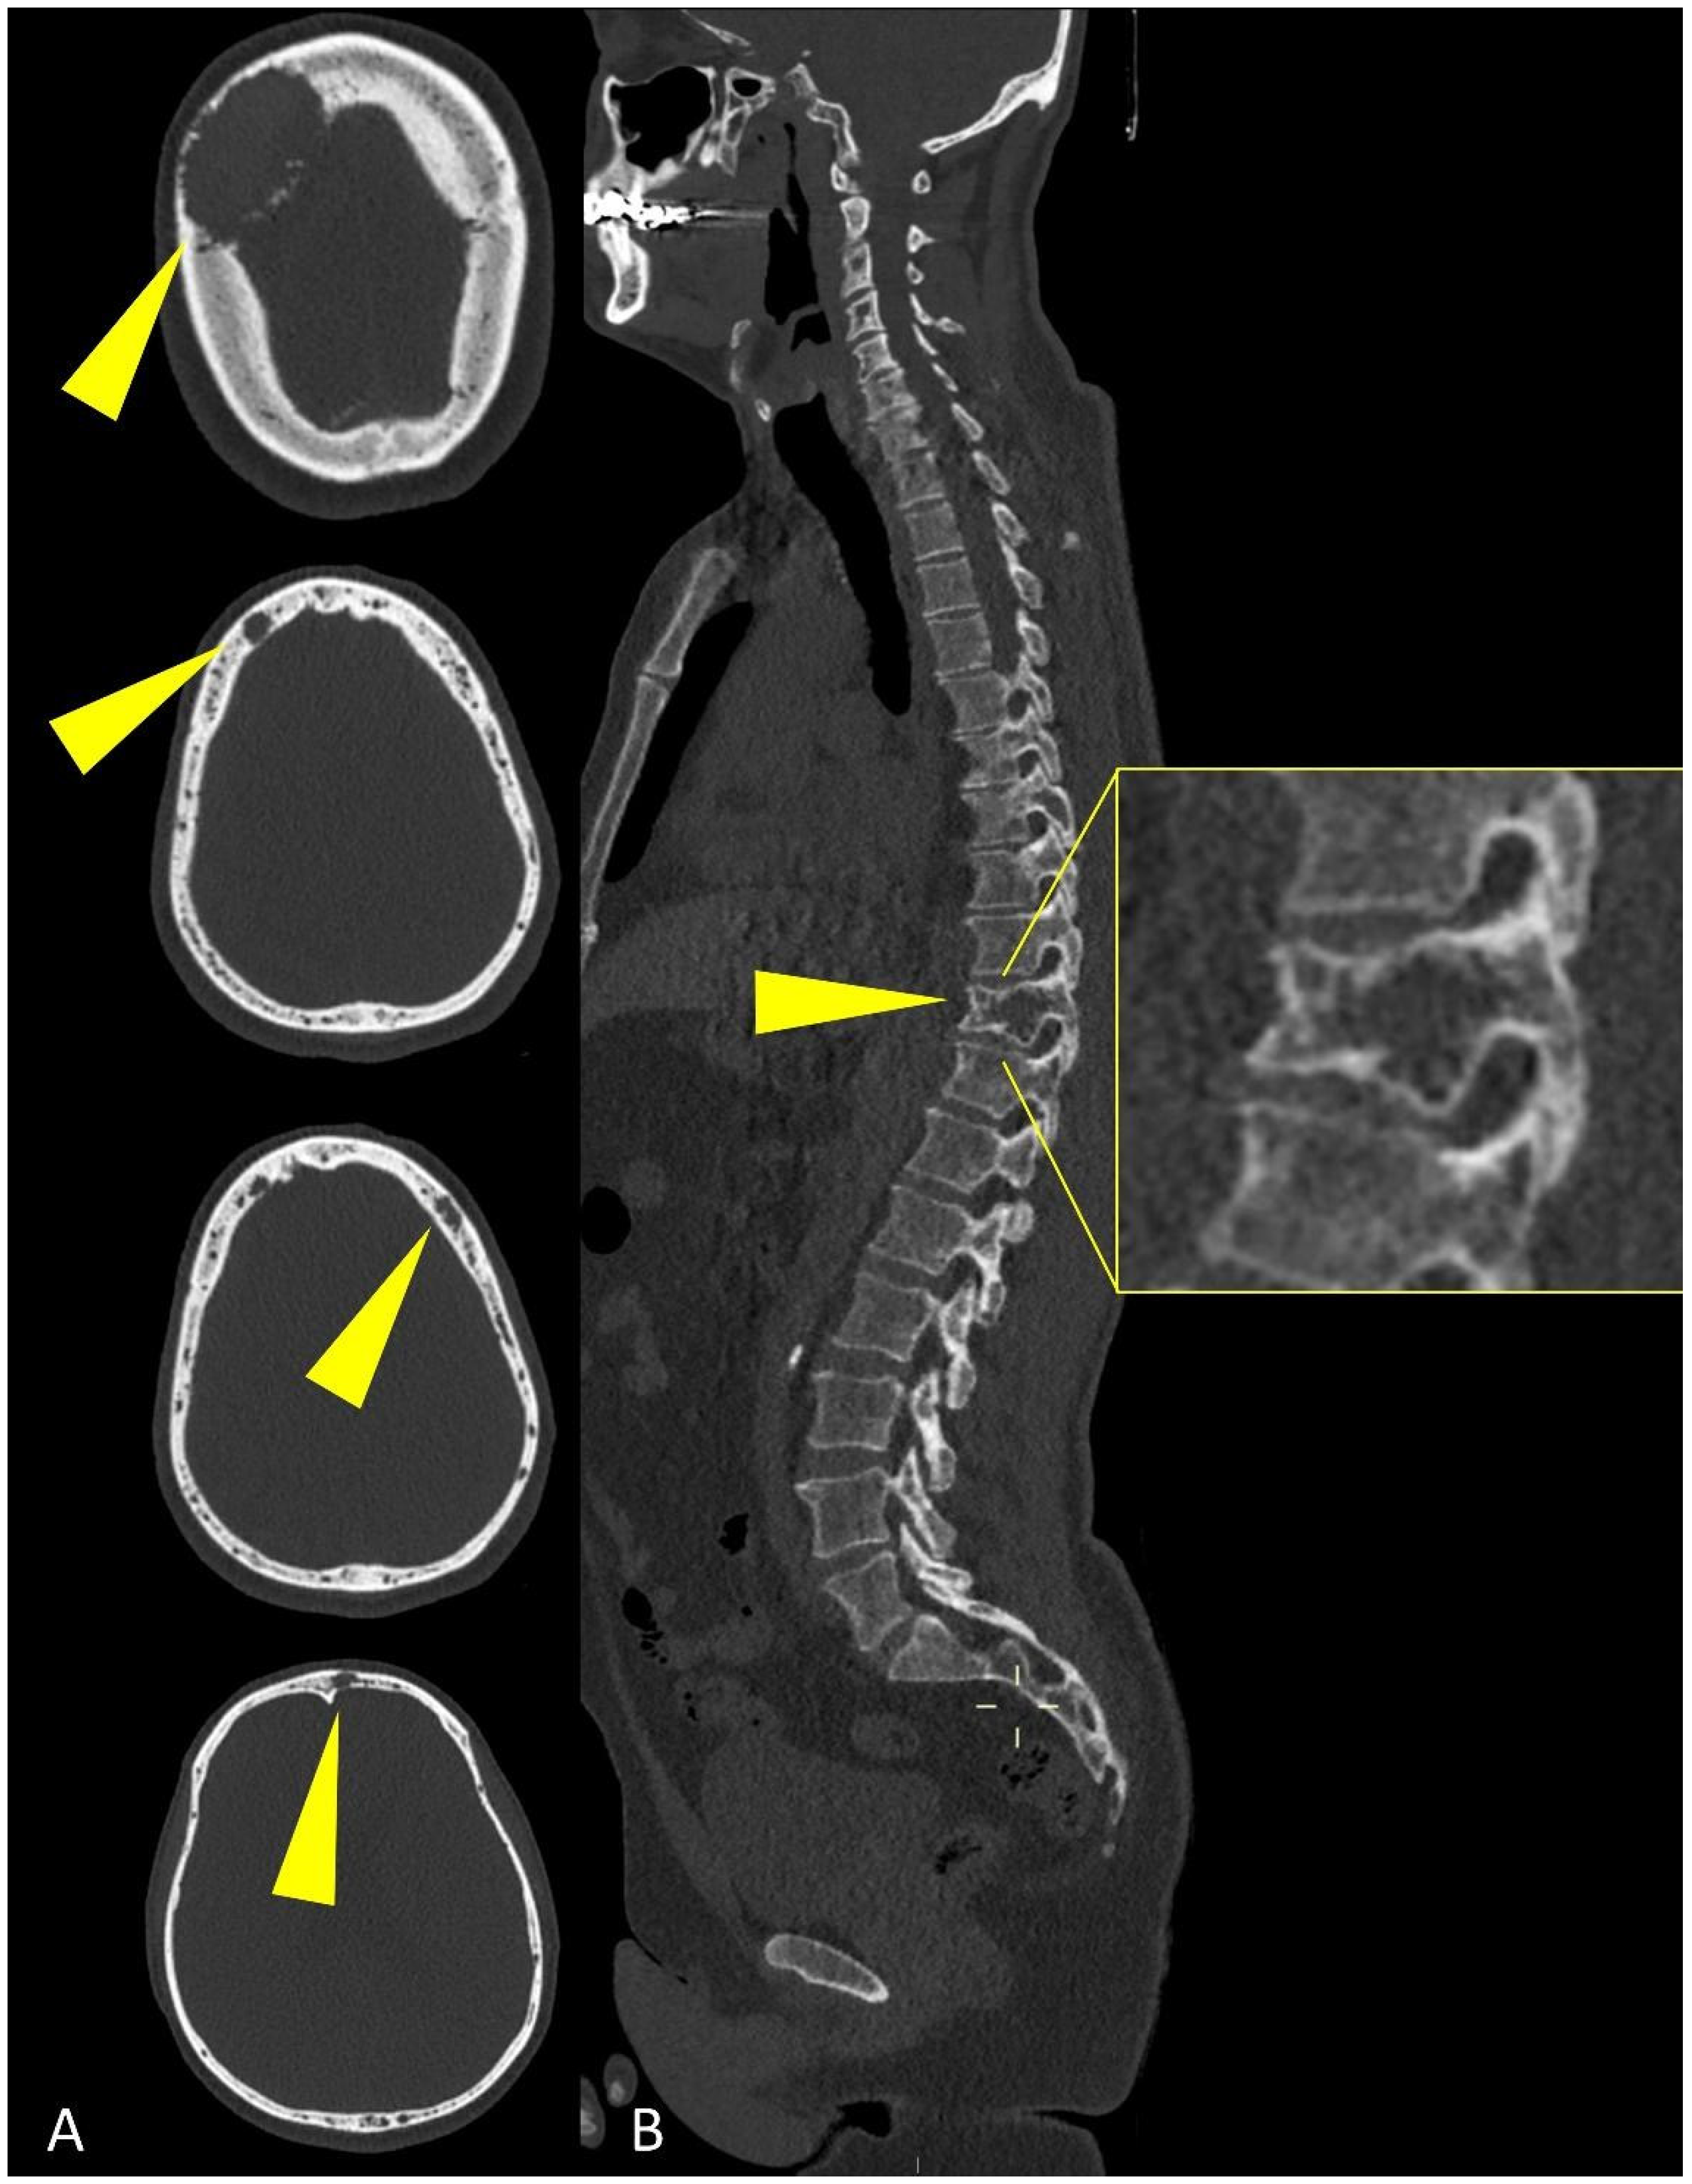

Whole-Body Low-Dose Multidetector-Row CT in Multiple Myeloma: Guidance in Performing, Observing, and Interpreting the Imaging Findings

3. WBLD-CT Imaging Findings and Evaluation